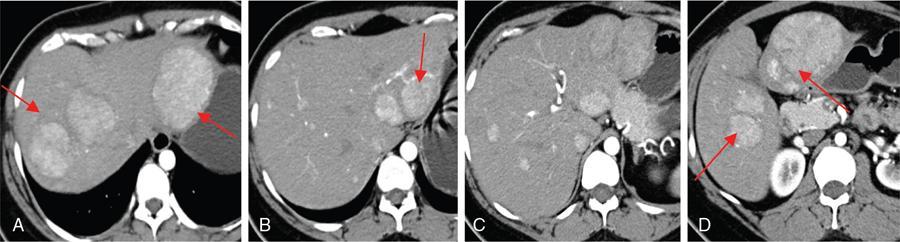

CT

MR